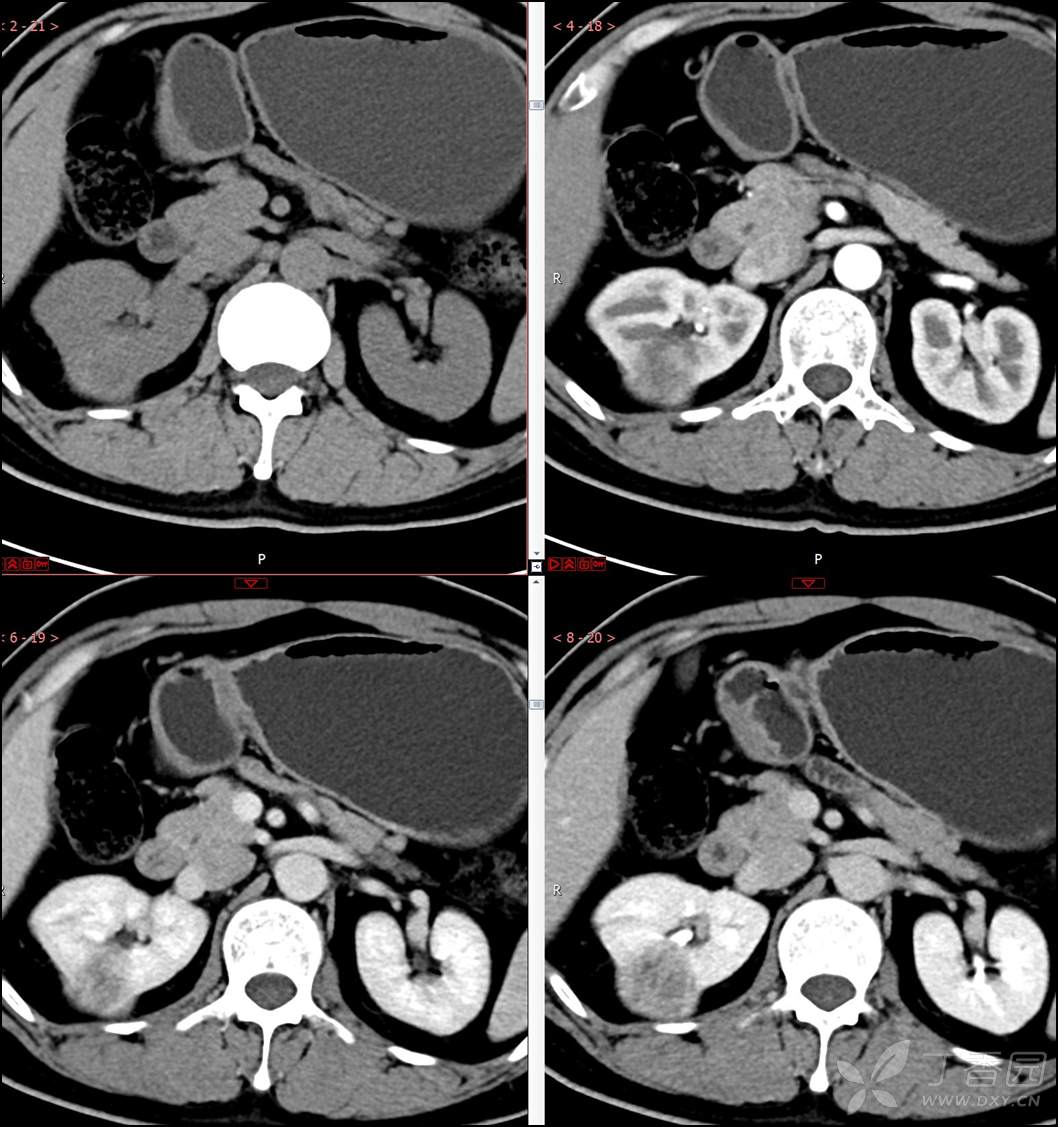

主诉:查体发现右肾肿物2月余

简要病史:患者2月余前于我院行健康查体,胸部(肺)CT平扫示:右肺中叶结节并右侧阻塞性肺炎;左肺上叶小结节;右肾占位。自诉无腰背部疼痛不适,无尿频、尿急、尿痛,无肉眼血尿,无恶心呕吐,无心悸、胸闷,无发热、寒战等不适,建议进一步检查。现患者为求进一步诊治于为我院就诊,建议手术治疗,门诊遂以“肾肿物(右)”收入院。患者自发病以来神志清,精神可,饮食可,睡眠欠佳,大便正常,体重近期无明显增减。